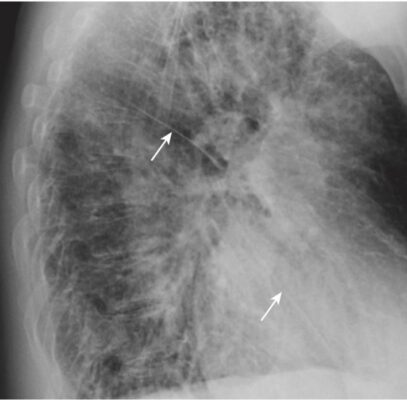

- Trên phim nghiêng, có thể nhìn thấy cả rãnh lớn (chéo) và bé (ngang) dưới dạng các đường nhỏ, màu trắng (dày khoảng bằng đường kẻ bằng đầu bút chì). Các rãnh phân định các thùy trên và dưới ở bên trái và các thùy trên, giữa và dưới ở bên phải.

- Các rãnh lớn chạy theo hướng chéo, khoảng từ mức của đốt sống ngực thứ 5 đến một điểm trên bề mặt cơ hoành của màng phổi sau xương ức vài cm. Rãnh bé nằm ngang mức xương sườn thứ 4 trước (chỉ có ở bên phải) và hướng theo chiều ngang (xem Hình 3).

- Có thể nhìn thấy cả rãnh lớn và rãnh bé trên phim nghiêng, nhưng do mặt phẳng chéo của rãnh lớn nên thường chỉ có thể nhìn thấy rãnh bé trên phim thẳng.

- Tùy thuộc vào độ dày của lát cắt, các rãnh sẽ có thể nhìn thấy dưới dạng các đường trắng mỏng hoặc bằng một dải vô mạch dày khoảng 2 cm khi chúng đi chéo qua phổi (Hình 16).

- Rãnh nhỏ đi cùng mặt phẳng ngang như với hình ảnh CT cắt ngang nên thường không thể nhìn thấy, ngoại trừ ở mặt phẳng đứng dọc hoặc mặt phẳng trán. Tuy nhiên, giống như các rãnh lớn, có thể suy luận ra vị trí của rãnh nhỏ bởi một vùng vô mạch giữa các thùy trên và thùy giữa phải (xem Hình 16, A).